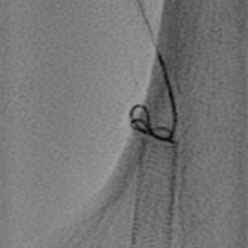

ONE CATHETER - MULTIPLE APPPLICATIONS

• 4 different needle protrusion lengths/shapes

• Needle protrusion length selector on handle